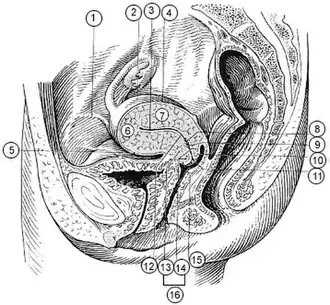

2. Ovário 3. Cavidade uterina 4. Tuba intestinal do útero 5. Pelvis vesical (voltada para a bexiga) 6. Fundo do útero 7. Corpo do útero 8. Palmate folds of cervical canal 9. Canal cervical 10. Lábio posterior 11. Cervical os (external) 12. Istmo do útero 13. Porção supravaginal do cérvix 14. Porção vaginal do cérvix 15. Lábio anterior 16. Cérvix | |

Secção sagital da parte inferior do tronco feminino, segmento direito

Secção sagital da parte inferior do tronco feminino, segmento direito -

Secção sagital mediana da pelve feminina.

Secção sagital mediana da pelve feminina.